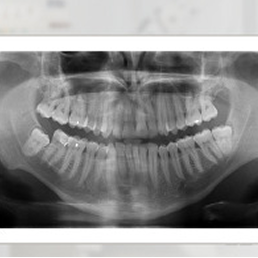

Examination package to diagnose the area of jaw, mandible, temporomandibular joints and maxillary sinuses.

X-ray examination showing the image of the jaw, mandible, temporomandibular joints and maxillary sinuses.

- Panoramic X-ray (panoramic radiograph) – an image of the entire oral cavity, covering the teeth, upper and lower jaws, and temporomandibular joints. Useful for general dental assessment and before prosthetic, surgical, or orthodontic treatment.